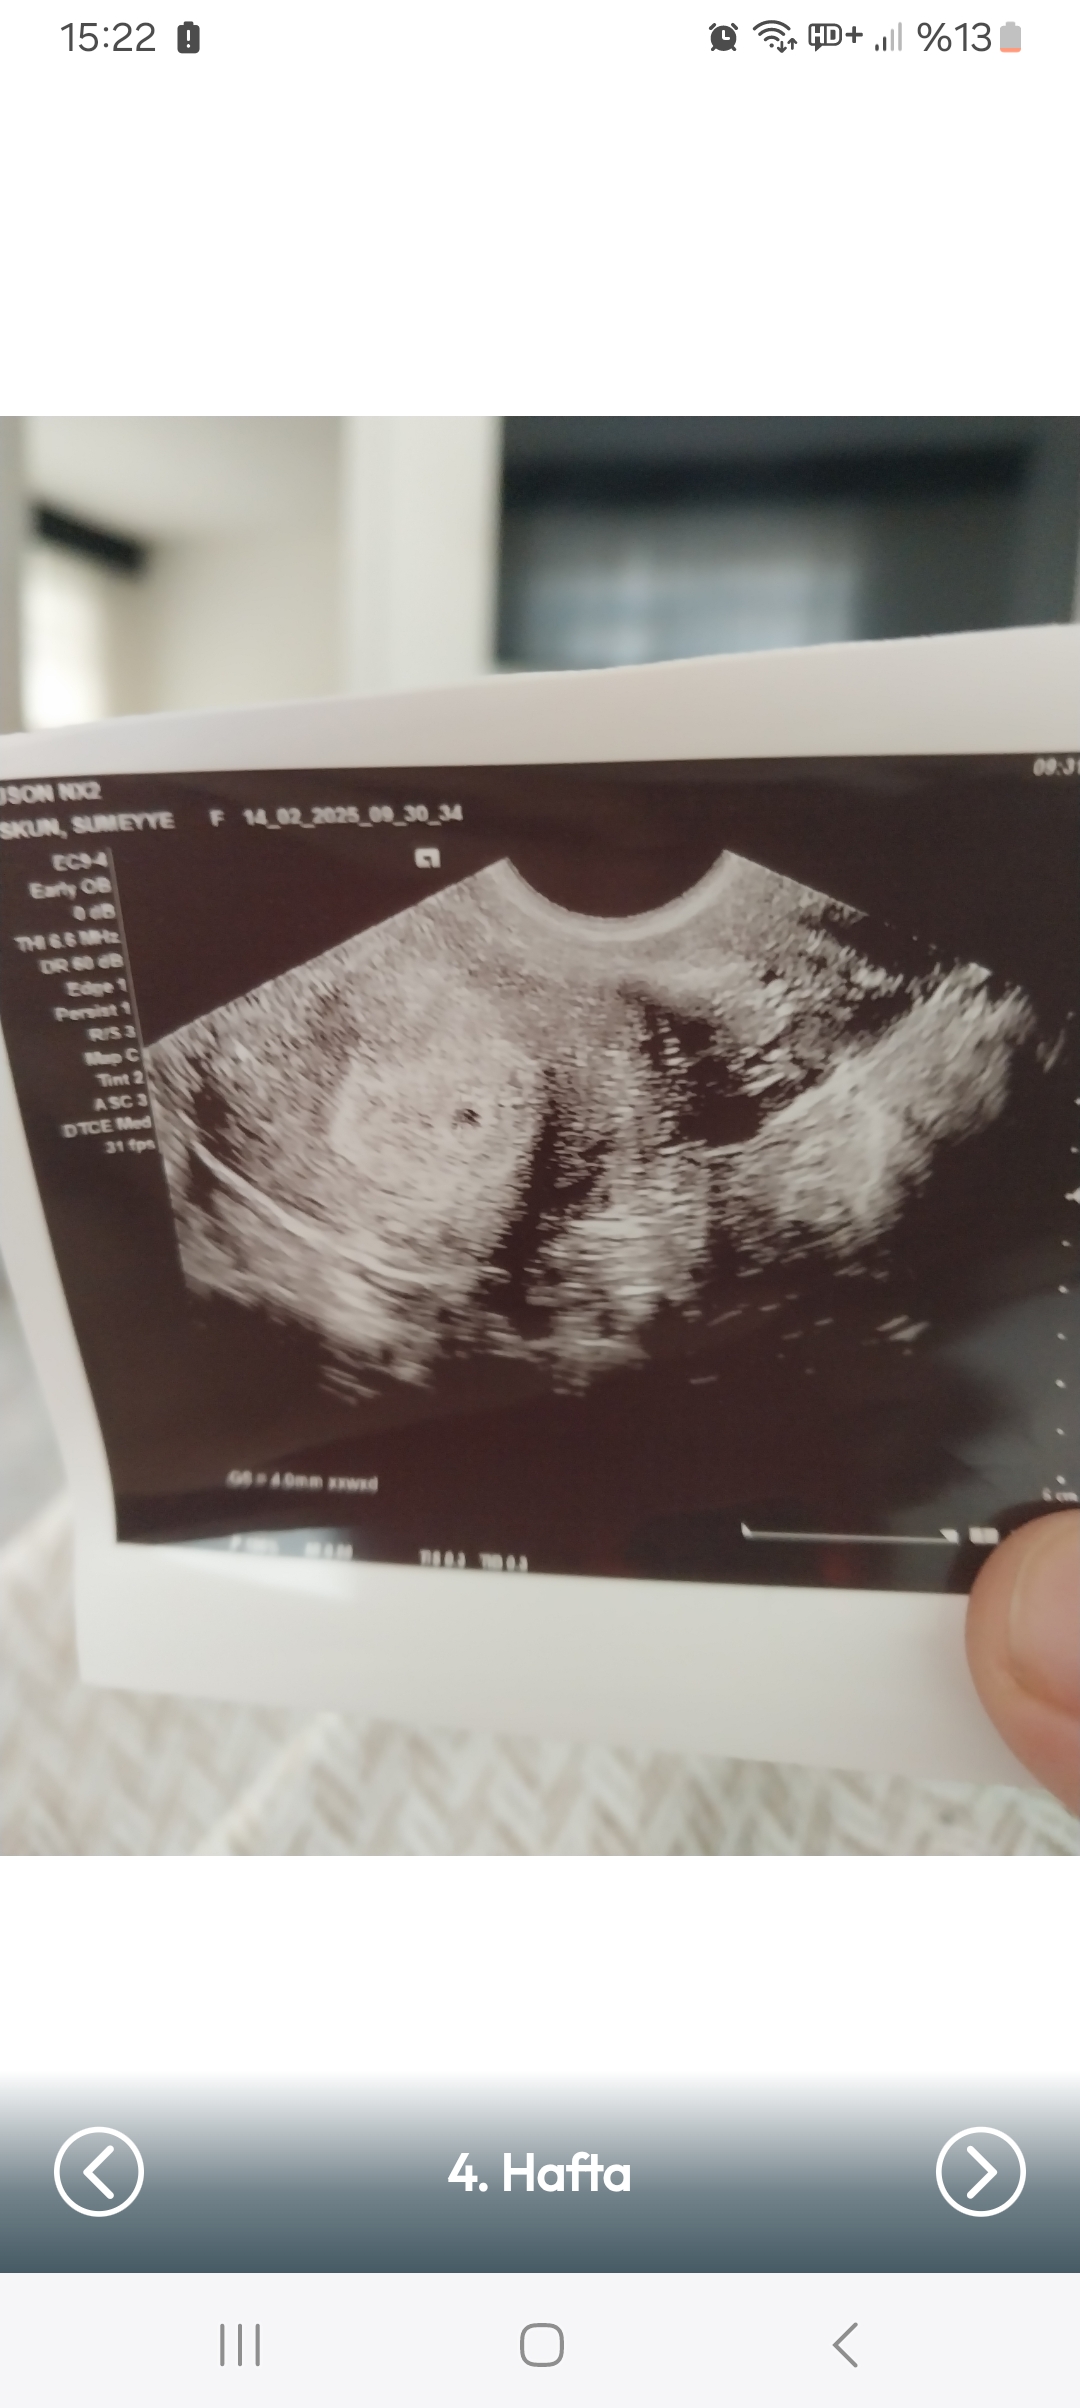

Cinsiyet tahmini

Konu Başlığı Cinsiyet tahmini